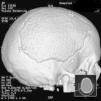

Caso 2. Adolescente de 16 años que ingresa en la UCI por fluctuación del nivel de consciencia en contexto de encefalitis. Consulta por fiebre, cefalea y diplopía. La TC muestra hipodensidad temporal derecha. El análisis del LCR fue normal, aunque con PCR a virus herpes simple tipo 1 (VHS-1) positiva. A las 24 horas inicia disminución del nivel de consciencia; se repite la TC que objetiva lesión temporal derecha cortical e importantes signos de edema cerebral e incipiente herniación (fig. 1A). Se coloca un sensor de PIC intraparenquimatoso que evidencia presiones de 30mmHg sin respuesta a medidas farmacológicas, por lo que se practica CD con apertura de la duramadre y buen control posterior de la PIC. A los 7 días se extuba y mantiene el nivel de consciencia conservado. La RM muestra cambios evolutivos secundarios a encefalitis herpética con abombamiento del parénquima a través de la craniectomía y mejoría de la compresión sobre el sistema ventricular (fig. 1B). Completa 21 días de tratamiento con aciclovir. Como secuelas neurológicas al alta destaca hemiparesia izquierda leve, paresia del sexto par craneal bilateral y epilepsia bien controlada con carbamazepina. A los 6 meses se realiza craneoplastia sin incidencias (fig. 2). Pasados 9 meses tras el ingreso, la paciente presenta una resolución de la hemiparesia y el estudio cognitivo es normal (leve déficit de memoria inmediata y comprensión lectora).